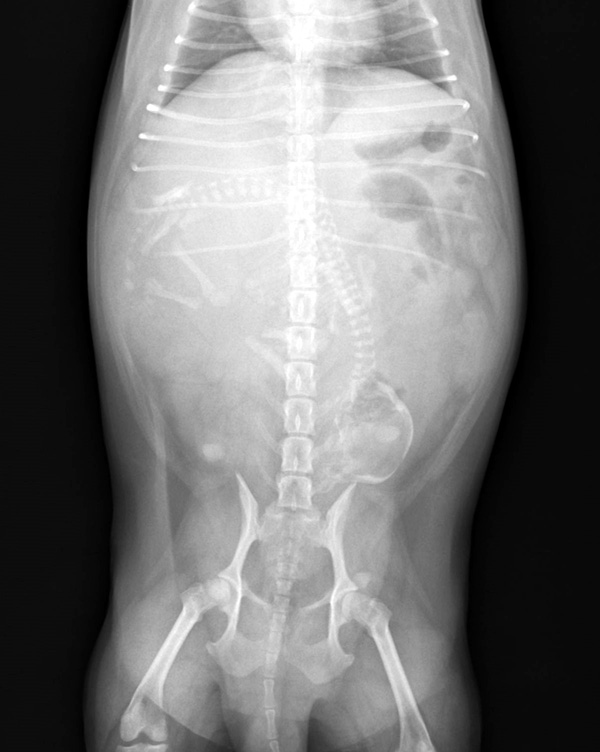

ポメラニアンちゃんの帝王切開でした。無事元気に生まれました。よかったね。